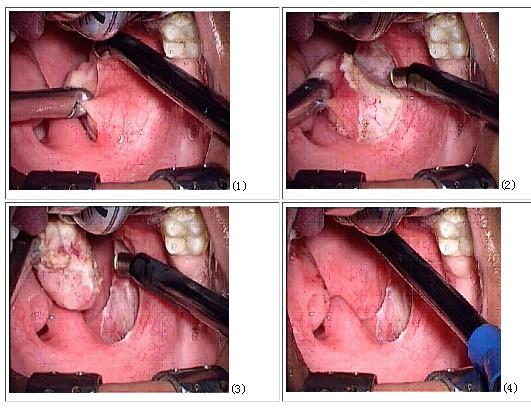

诊断 处理 诊断:右腭部肿瘤 治疗:全麻下行腭部肿瘤切除,术中冰冻

共收录 7197 个手术 腭部良性肿瘤切除术用于腭部良性肿瘤的治疗